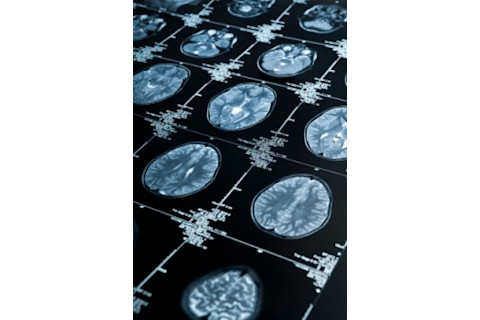

研究人员对 24 名参与者进行了fMRI扫描,这种扫描可以测量大脑中的血流量。他们追踪了参与者的大脑活动,当时他们的一小部分前臂暴露在热度下,这种热度要么是痛苦的(非常热),要么是不痛苦的(令人愉悦的温暖)。然后,一个计算机算法分析了数据中的模式,寻找响应于疼痛或非疼痛热的脑部活动类型。

接下来,该团队让另外 16 个人做了同样的事情,在他们的手臂暴露于不同程度的热度时,对他们的大脑进行了扫描。这一次,研究人员使用了计算机算法——现在它已经接受了之前受试者的数据训练——来分析扫描结果,根据脑部活动将每次热暴露分类为疼痛或非疼痛。计算机模型可以正确地识别出 81% 的疼痛体验。